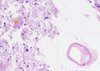

Atherosclerosis of the Artery

Adventitia

Atheroma

Clefts after washing up Cholesterol Crystals

Granular Deposits of Calcium

Intima

Lipophages

Lumen and Fibrous Cap

Lymphocytes

Media

Necrotic Detritus

New Blood Vessels